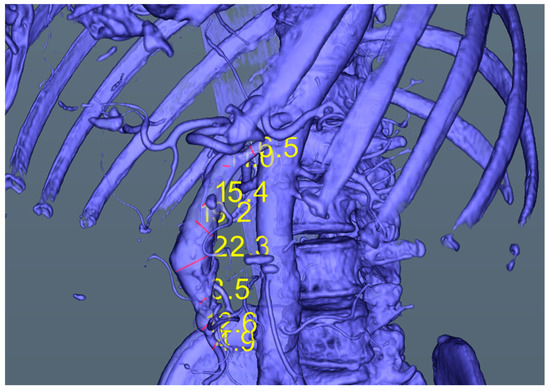

• Automatic measurements of the artery diameter in “healthy” zones and aneurysm zone (see Figure 8 and Table 1)

The automatic measurements are in fact the values of the artery diameter computed automatically in points either chosen by the user or along the virtual angiography path.

Figure 8. Measurements in the virtual 3D scene along the mesenteric artery aneurysm.

Table 1. Automated measurements along the aneurysm, opposite the direction of the blood flow, starting and ending with “healthy” zones.

Entry Point—Healthy ZoneAneurysm ZoneExit Point—Healthy Zone

4.912.6 13.5 22.3 19.2 15.4 11.06.5